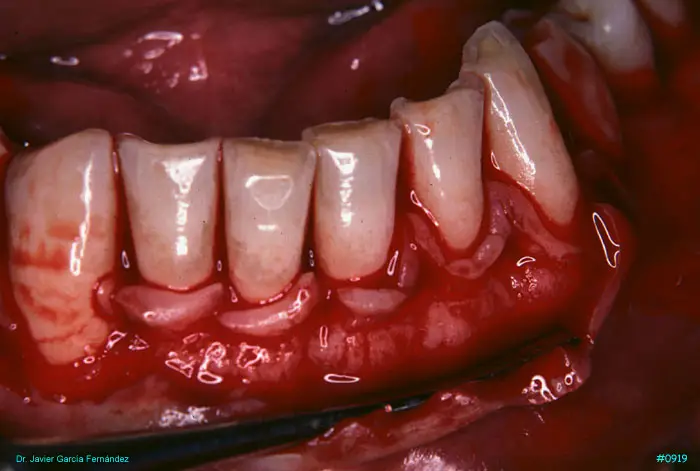

Atlas of Surgical Techniques in Periodontics. Chapter III. Atlas de Técnicas Quirúrgicas en Periodoncia